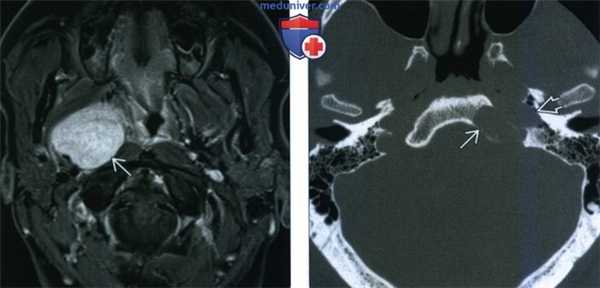

(Слева) МРТ Т1ВИ FS c КУ, коронарная проекция. В сонном пространстве определяется накапливающее контраст новообразование. В толще опухоли имеются участки кистозного перерождения, которые весьма характерны для шванном. Характерно смещение внутренней сонной артерии в медиальную сторону.

(Справа) КТ с КУ, аксиальная проекция. В надподъязычном отделе сонного пространства визуализируется шваннома, интенсивно накапливающая контраст. Внутренняя и наружная сонные артерии смещены в медиальную сторону, что характерно для шванном. Внутренняя яремная вена в редких случаях смещается кпереди. Если шваннома богато кровоснабжается, то по своему виду она может напоминать параганглиому.

(Справа) КТ в костном окне, аксиальная проекция. Фестончатые изменения костных структур в области ската характерны для шванном. Шваннома, локализующаяся в носоглоточном отделе сонного пространства, может ремоделировать костную ткань основания черепа. Для параганглиом, напротив, характерен деструктивный рост.